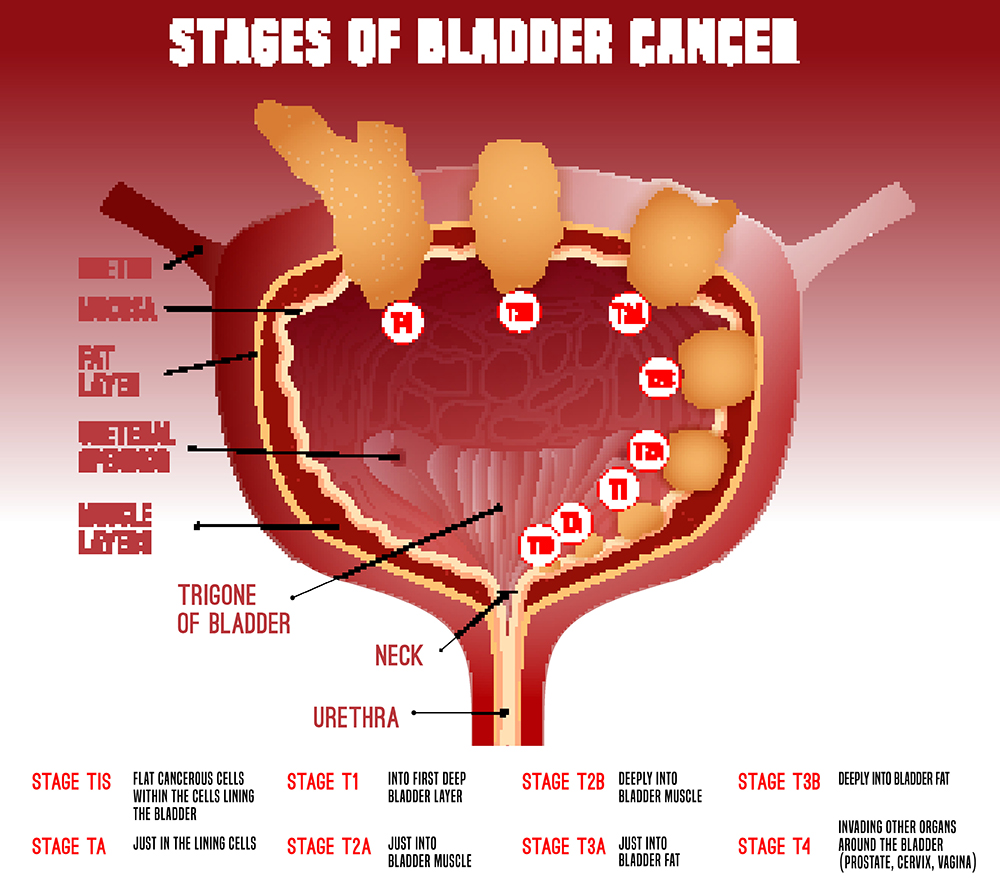

Illustration of different pathological stages of bladder cancer. Stage …

Classification Of Bladder Tumors : TNM stage classification of bladder …

Stages of bladder cancer from Meyer et al., (2002). Bladder cancer can …

Overview of staging and grading of bladder cancer tumor. The figure was …

Classification Of Bladder Tumors : TNM stage classification of bladder …

Bladder Cancer Staging | MedicineBTG.com